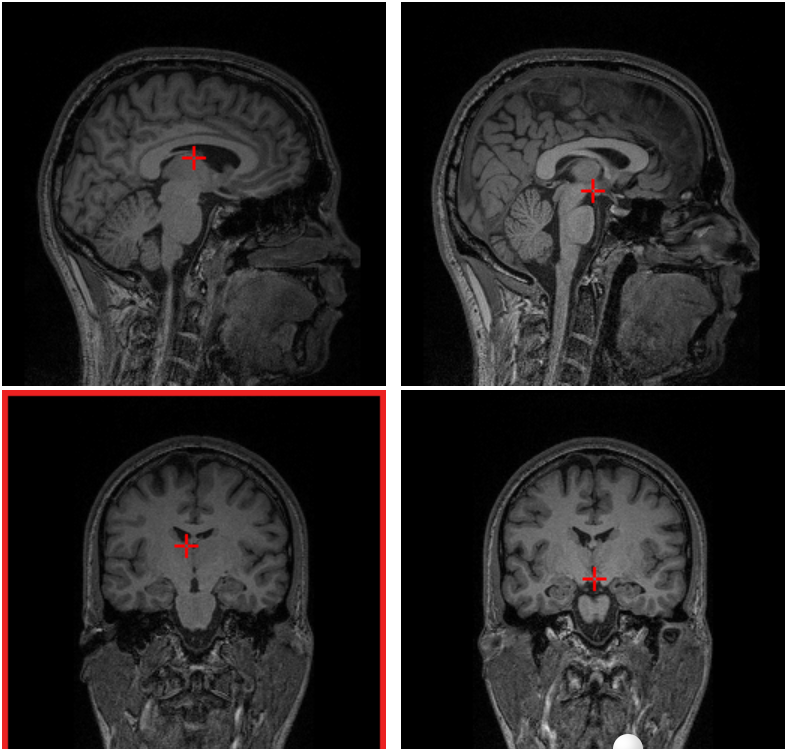

Привет! На связи сообщество Нейрофизиология. На нашем сайте мы добавили очень полезный раздел с инструментами, где любой человек может посмотреть свои анализы МРТ/КТ/ПЭТ, без скачивания каких-либо программ.

Там же можно найти 500 мегабайт снимков МРТ людей для изучения (спасибо университету McGill). Будет очень полезно студентам-медикам и интересующимся.

Когда при нажатии на изображение мозга (Shift+клик) оно подсвечивает другие его области — это, скорее всего, отображение анатомических коррелятов или связей между различными областями мозга. Это означает, что выбранная вами область связана с определёнными функциями, симптомами или другими структурами.